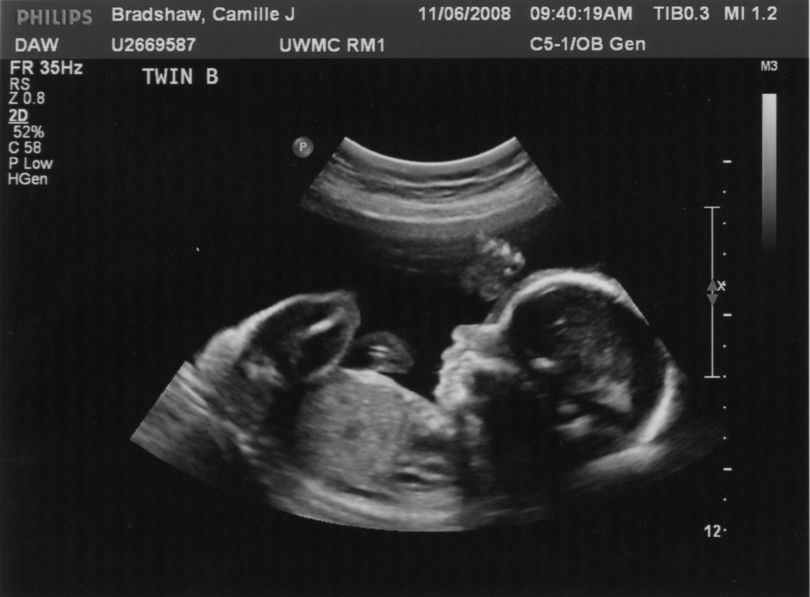

Ultrazvočna diagnostika med nosečnostjo je nepogrešljiva metoda za spremljanje razvoja in morebitnih anomalij pri plodu. Strokovnjake pa vednar vedno bolj skrbi varnost nepotrebnega fotografiranja otrok, ki jih starši želijo za spomin. Ultrazvočna energija zaradi natančnejšega posnetka otrokove glavice tako deluje dlje časa.